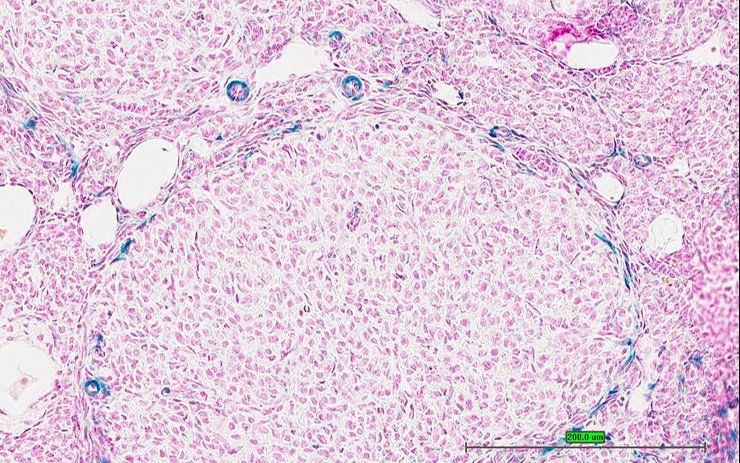

TS28: spleen Present UC Davis_1889602

Specimen UC Davis_1889603: postnatal adult; Cacnb2tm1.1(KOMP)Vlcg/Cacnb2+ (more )

Structure Level Pattern Image Note

TS28: spleen Present UC Davis_1889603

TS28: spleen Present UC Davis_1889525

Specimen UC Davis_1889526: postnatal adult; Cacnb2tm1.1(KOMP)Vlcg/Cacnb2+ (more )

TS28: spleen Present UC Davis_1889526